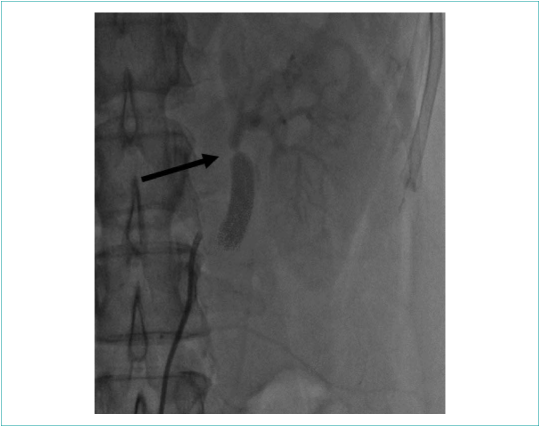

Выполнена ангиография почечных артерий, по результатам которой выявлен 95 % стеноз в дистальном отделе левой почечной артерии сразу за дистальным анастомозом шунта, в правой почечной артерии гемодинамически значимых стенозов не выявлено (рис. 2, 3).

Рисунок 2. Ангиография левой почечной артерии (95 % стеноз указан стрелкой)

Picture 2. Left renal artery angiography (95% stenosis indicated by arrow)